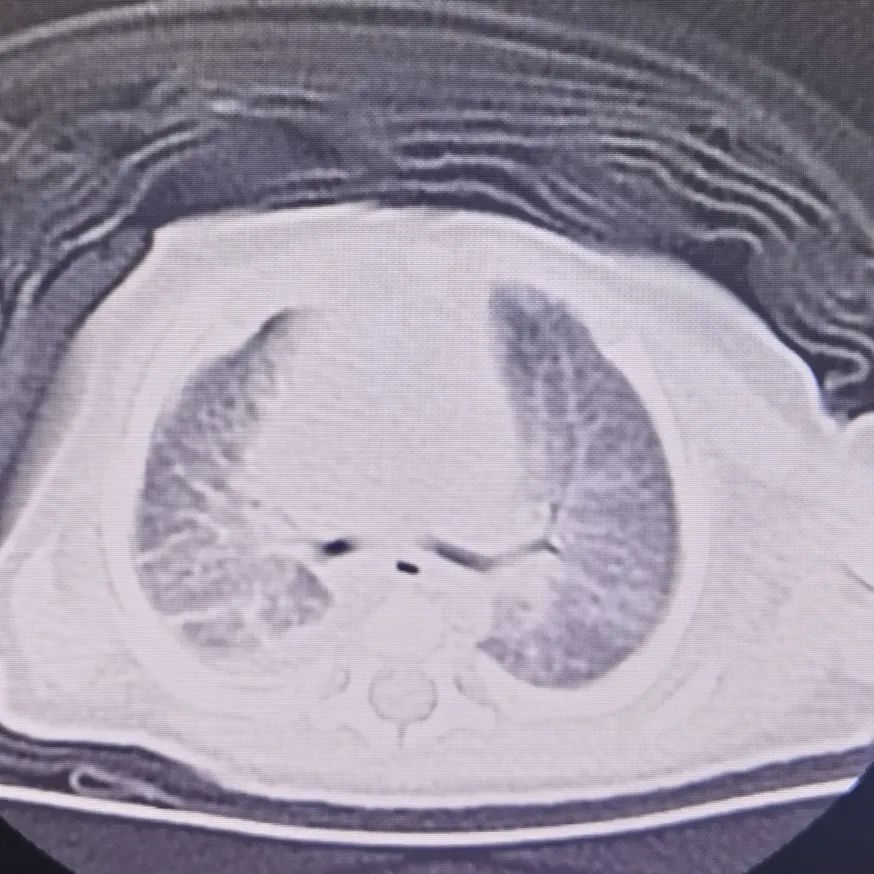

术后胸部CT

手术开始了,早产儿的胸腔镜耐受能力还是差了些,只能接受2mmHg压力的二氧化碳气体,再提高压力,患儿的氧合能力就开始下降。在狭小的胸腔环境里,每一个动作都不能有分毫偏差,任何副损伤都会加重病情。王莹凭借过硬的微创手术经验,谨慎分离胸腔内粘连组织。荧光导航下,病灶界限清晰可见,超声刀精准完整切除病灶。郭海娟紧密配合,即刻恢复双肺通气,王莹再用胸腔注水实验仔细检查有无气漏。短短1小时,手术顺利结束。麻醉清醒后,小云儿脱离呼吸机,平安回到新生儿重症监护室进一步观察。

术后 1 周,小云儿顺利拔出胸腔闭式引流管,脱离鼻导管吸氧。在全体医护人员的精心呵护下顺利出院。爸爸妈妈抱着小云儿,心中满是感激与幸福:“感谢新生儿外科医护团队,让这个家终于完整了!是你们让我们知道,孩子的病虽然凶险,但找对科室就有希望!”